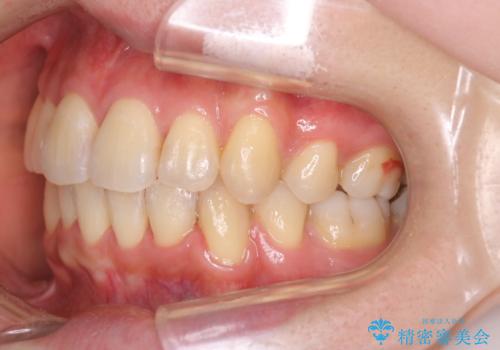

ガタガタの抜歯矯正を裏側ワイヤーを使っての目立たない矯正

- 八重歯とガタガタを主訴に来院されました。

目立たないワイヤー矯正を希望されたので、上下左右のはを1本ずつ抜歯して、ハーフリンガル(上顎だけ裏側)にて矯正をすることにしました。